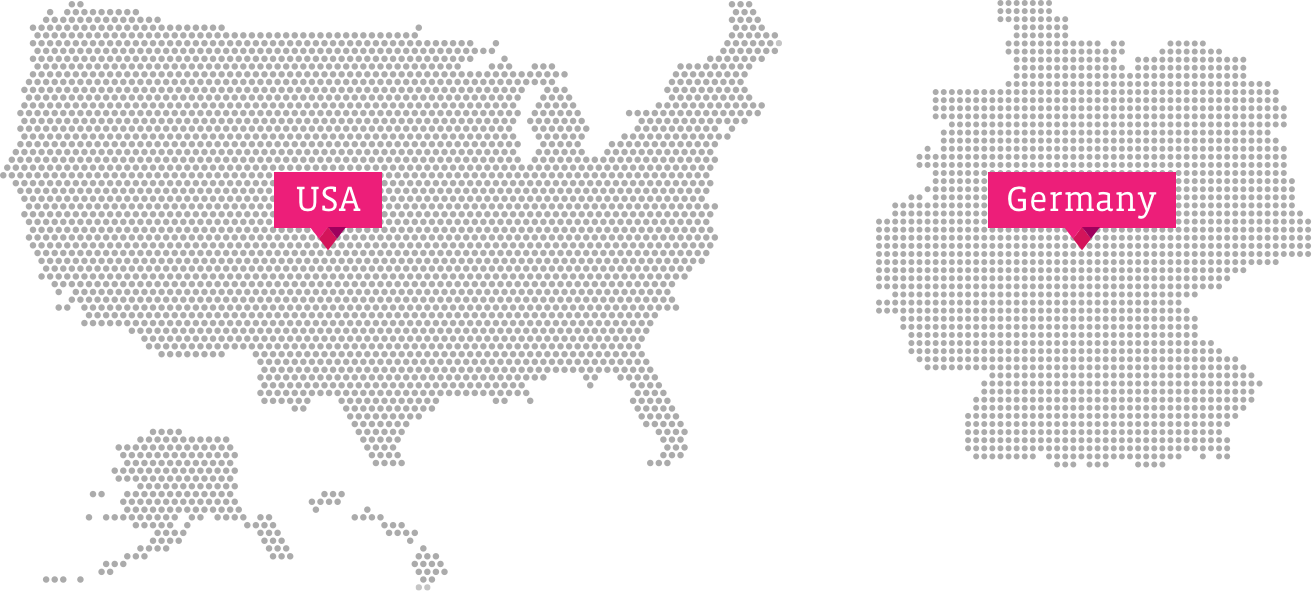

Seattle, WA, USA

Thousand Oaks, CA, USA

Rochester, MN, USA

Detroit, MI, USA

Cincinnati, OH, USA

Nashville, TN, USA

Wynnewood, PA, USA

New York, NY, USA

Stony Brook, NY, USA

Mainz, Germany

Leipzig, Germany

Berlin, Germany